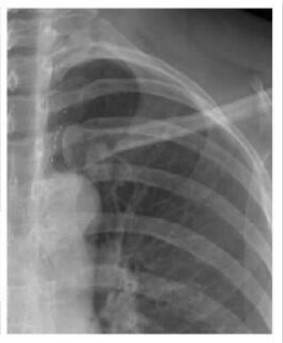

案例二:

图二 左锁骨重叠致密结节,误为衣服纽扣,病理肺腺癌

案例解析:

该病例发生在国内某基层医院,病患首先通过胸片摄影筛查,显示出左上肺野内带高密度椭圆形结节,由于形状与纽扣极为相似,误为衣服纽扣,并未做进一步诊断。第二年之后,病患再来复查,却发现照片上结节影增大,立即进一步诊断检查,最终经过活检证实为肺癌,错过了最佳的肺癌治疗期。